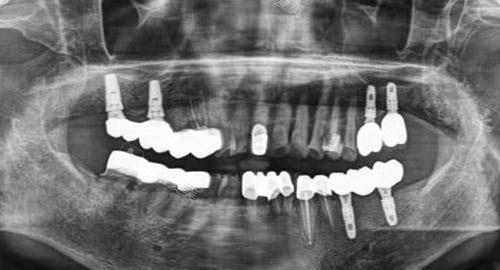

多颗牙齿种植ct

在复杂修复领域,像牙齿种植、牙齿正畸等,医师团队会根据患者的具体情况,结合较高的技术和设备,制定科学合理的修复方案。